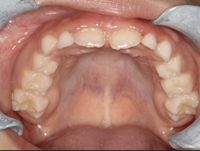

En el examen intraoral se observa mordida cruzada anterior. Las líneas medias dentales coinciden. Esto indica correcta alineación central. Tanto el arco superior como el inferior presentan forma en U, lo que sugiere un buen espacio para la dentición y una correcta disposición de los dientes en ambos arcos.

Figura 4. Mordida cruzada anterior Figura 5. Arco superior en forma de U

Figura 6. Arco interior en forma de U